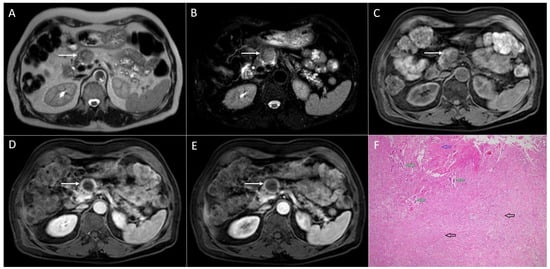

3.4. Pancreatic Metastases